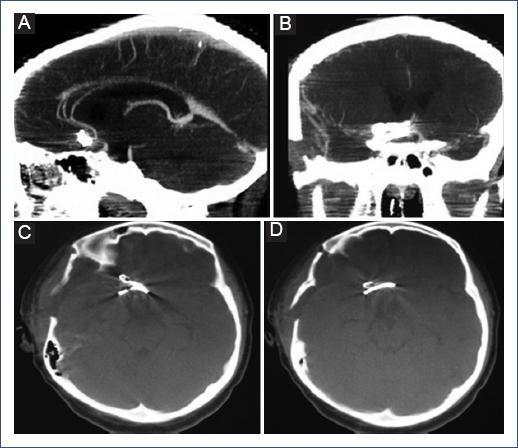

The patient was awake, with a tendency to somnolence, reactive isochoric pupils (3 mm), without cranial nerve involvement, left body hemiparesis with strength 4/5. She presented the following scores: on the Glasgow Coma Scale, 12 points (O3, V4, M5); on the World Federation of Neurologic Surgeons scale (WFNS), grade IV; on the Hunt and Hess scale, grade 3, and on the Fisher scale, grade 4 (by tomography). Management was decided in the Pediatric Intensive Care Unit (PICU) to ensure stability, and clipping of the aneurysm was performed by right pterional craniotomy two weeks after the event (Figure 2). The patient was extubated 72 hours after the procedure and subsequently returned to the ward for continued management.

On day 7, a postoperative CTA was performed, which showed adequate clipping and exclusion of the aneurysm (Figure 3). The patient was evaluated by Rheumatology, Cardiology, Neurology, Infectology, and Genetics, performing whole body CTA, echocardiography, bilateral renal ultrasound, and immunological tests. However, it was not possible to identify the etiology of the aneurysm. She was discharged on postoperative day 8 with an antiepileptic drug and resolution of symptoms. She is currently asymptomatic with outpatient follow-up.